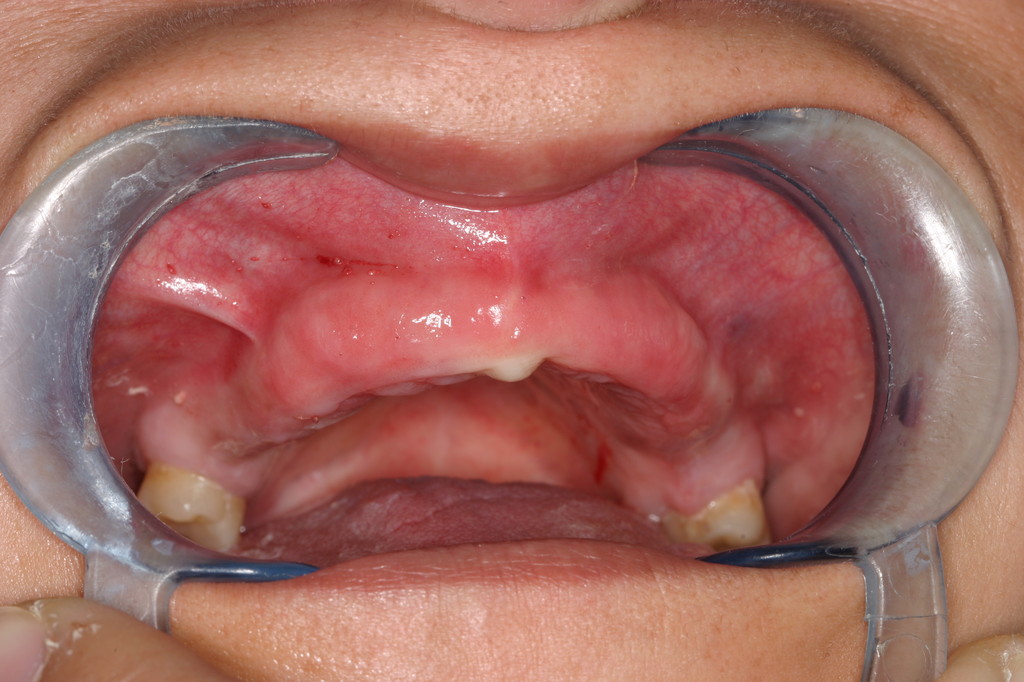

REHABILITACIÓN CON IMPLANTES ,ENFERMEDAD PERIODONTAL AVANZADA.

REHABILITACIÓN IMPLANTOSORTADA EN MANDÍBULA Y MAXILAR.